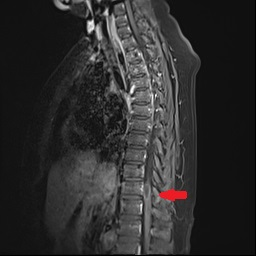

患者康婆婆(化名)今年已近70岁,因“右下肢麻木5+月加重伴疼痛3+月”前来医院治疗,行腰部核磁检查发现胸11椎体平面脊髓内囊性占位,考虑室管膜瘤的肿瘤性病变。患者下肢长期麻木伴疼痛,经神经外科医疗团队研究讨论,为患者行了微创的胸椎椎管骨质切开和脊髓内肿瘤病变的切除手术治疗,切除了患者的肿瘤后,患者下肢肌力和麻木感明显改善。

手术前检查